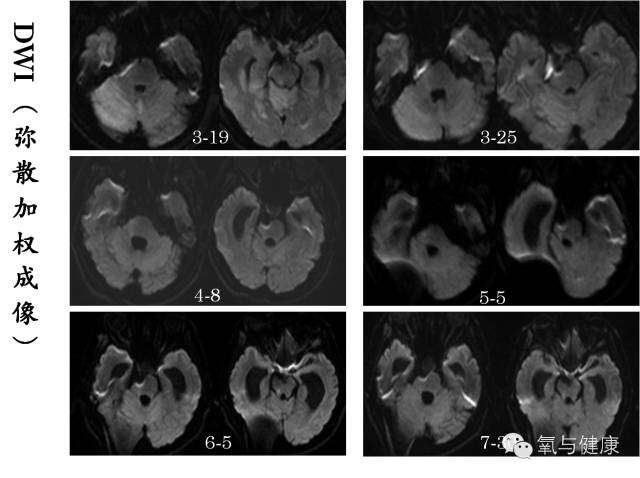

2014年3月12日下午5:20,北京天坛医院,一位男性患者,43岁,因突然出现昏迷,呼吸暂停正在紧急抢救。经紧急气管插管,呼吸机支持等抢救措施,待生命体征平稳后,急诊脑CT检查,确诊为颅内蛛网膜下腔出血,考虑动脉瘤破裂。于19:21分行脑血管介入造影,确诊为基底动脉尖夹层瘤破裂,并行动脉栓塞术。术后自主呼吸恢复,但仍呈浅昏迷状态,随后转入重症监护病房监护治疗,同时进行脑室和腰穿引流,颅内压监测。3月16日(术后第四天)患者昏迷状态加重,医院组织神经外科、神经内科、神经介入科、神经ICU和高压氧科等有关专家紧急会诊。经专家讨论认为再出血可能性很小,除加强监护治疗外,应尽早高压氧治疗。鉴于患者随后两日昏迷进行性加重,3月19日脑核磁影像发现右侧中脑、桥脑和小脑引部和半球广泛急性缺血改变,为挽救患者缺血区脑组织,改善脑干功能,随紧急于当日采用高压氧舱内抢救治疗。高压氧首次治疗后次日患者意识即出现明显好转,随后每次治疗后均有明显改善,后经经高压氧连续治疗6次后神志完全清醒,3月25日、4月8日及5月份脑核磁影像检查原脑缺血范围和程度明显好转(详见核磁影像对比)

3月19日患者意识障碍加重,脑核磁显示:小脑及右侧颞叶可见大片状水肿T2/FLAIR呈稍高信号,DWI呈稍高信号,提示小脑及右侧颞叶大片组织急性缺血性改变,无明显活动性出血;

3月25日和4月8日患者脑核磁复查显示:小脑及右侧颞叶可见大片状水肿T2/FLAIR呈稍高信号,DWI呈稍高信号逐渐减低,范围逐渐缩小,4月8日时DWI信号恢复正常。